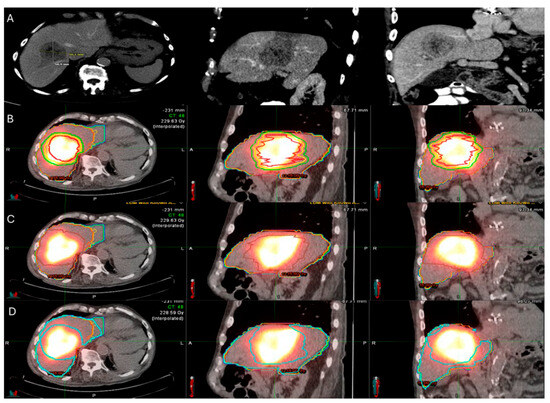

Evidence from RS studies also supports the dose–response relationship. In a small series of 36 patients with hepatic metastases (11 CLM; 31%) undergoing RS with target radiation dose > 200 Gy resulted in 92% local disease control rate; 28% of the patients ultimately progressed at a median follow-up of 12 months [148]. Another small case series of 10 hepatic metastases including 7 CLM indicated that a mean tumor absorbed dose of 251.7 Gy, achieving a local disease control rate of 85.8% [147]. According to the previously mentioned single center RS study including exclusively patients with CLM, a mean tumor absorbed dose ≥400 Gy and a 5 mm margin around the tumor mean absorbed dose ≥350 Gy; the LTP rate was 16.7% in contrast to 86% LTP rate of the cases with lower doses (Figure 5) [149].

Figure 5.

60-year-old male with history of Neuroblastoma Rat Sarcoma (N-RAS) mutant rectal adenocarcinoma with bilobar liver metastases and prior systemic chemotherapy, right hepatectomy, and left metastasectomies, presents with new metastasis in close proximity to the left portal vein deemed high risk for thermal ablation (A–C). After multidisciplinary review, radiation segmentectomy was recommended as the appropriate therapy to minimize the risk for injury of the nearby portal vein ((A) orange arrowhead indicates the left branch of portal vein, green arrowhead indicates the target tumor). During mapping, CT arteriography demonstrates optimal tumor coverage (D) confirmed by Technetium-99m Macroaggregated Albumin (Tc-99m-MMA SPECT/CT) (E). CT arteriography during TARE (F) and post-TARE bremsstrahlung scan (G) demonstrates optimal target tumor coverage (E,G): the red circle represents the tumor contours, while the yellow the 5 mm and the green the 10 mm margin areas around the target tumor. The mean tumor absorbed dose is 1611.8 Gray (Gy), the mean 5 mm absorbed dose 1210.3 Gy, and the mean 10 mm margin absorbed dose is 923.8 Gy according to dosimetry workflow of MIM DEV version 3.3.7. (H). Follow-up ceCT at 2 years indicates sustained long-term tumor control (I).

There are different methods used to calculate the 90Y administration dose. The initially reported method of dosimetry was utilizing the Body Surface Area (BSA) model. This technique, commonly used for SIR-spheres, calculates the prescribed dose using the BSA and the tumor burden within the target liver parenchyma [163,164]. In an effort to increase the ability of operators to provide personalized dosimetry based on tumor characteristics and therapeutic intent, a small patient trial of 15 patients using Tc99-MAA for LSF calculation, CT to calculate liver volume, and post-TARE bremsstrahlung scan for actual 90Y delivery location confirmation, generating the Medical Internal Radiation Dose (MIRD) model [165]. MIRD utilization is recommended by Thera-sphere manufacturers and was also used in the EPOCH trial. Main limitation derives from the fact that it is a single-compartment model, which contains both the target tumor and surrounding healthy parenchyma (Figure 6). Dose volume histogram (DVH) curves that display the dose distribution within the different generated compartments and the included structures and tumor (Figure 7).

Figure 6.

86-year-old with synchronous relatively large metastasis in the right lobe on pre-treatment ceCT (A) undergoes radiation segmentectomy. Post-TARE Medical Internal Radiation Dose (MIRD) dosimetry is demonstrated according to the workflow using MIM DEV software version 3.3.7 using the post-TARE bremsstrahlung scan (B–D). The contours of the treated tumor are illustrated by the red line; yellow circle represents the 5 mm margins, and the green circle represents the 10 mm margins around the target tumor (B). The area defined by the brown circular line represents the single compartment used by the MIRD method that contains the target tumor (C). The area enclosed by the blue line represents the non-tumor liver parenchyma (D).